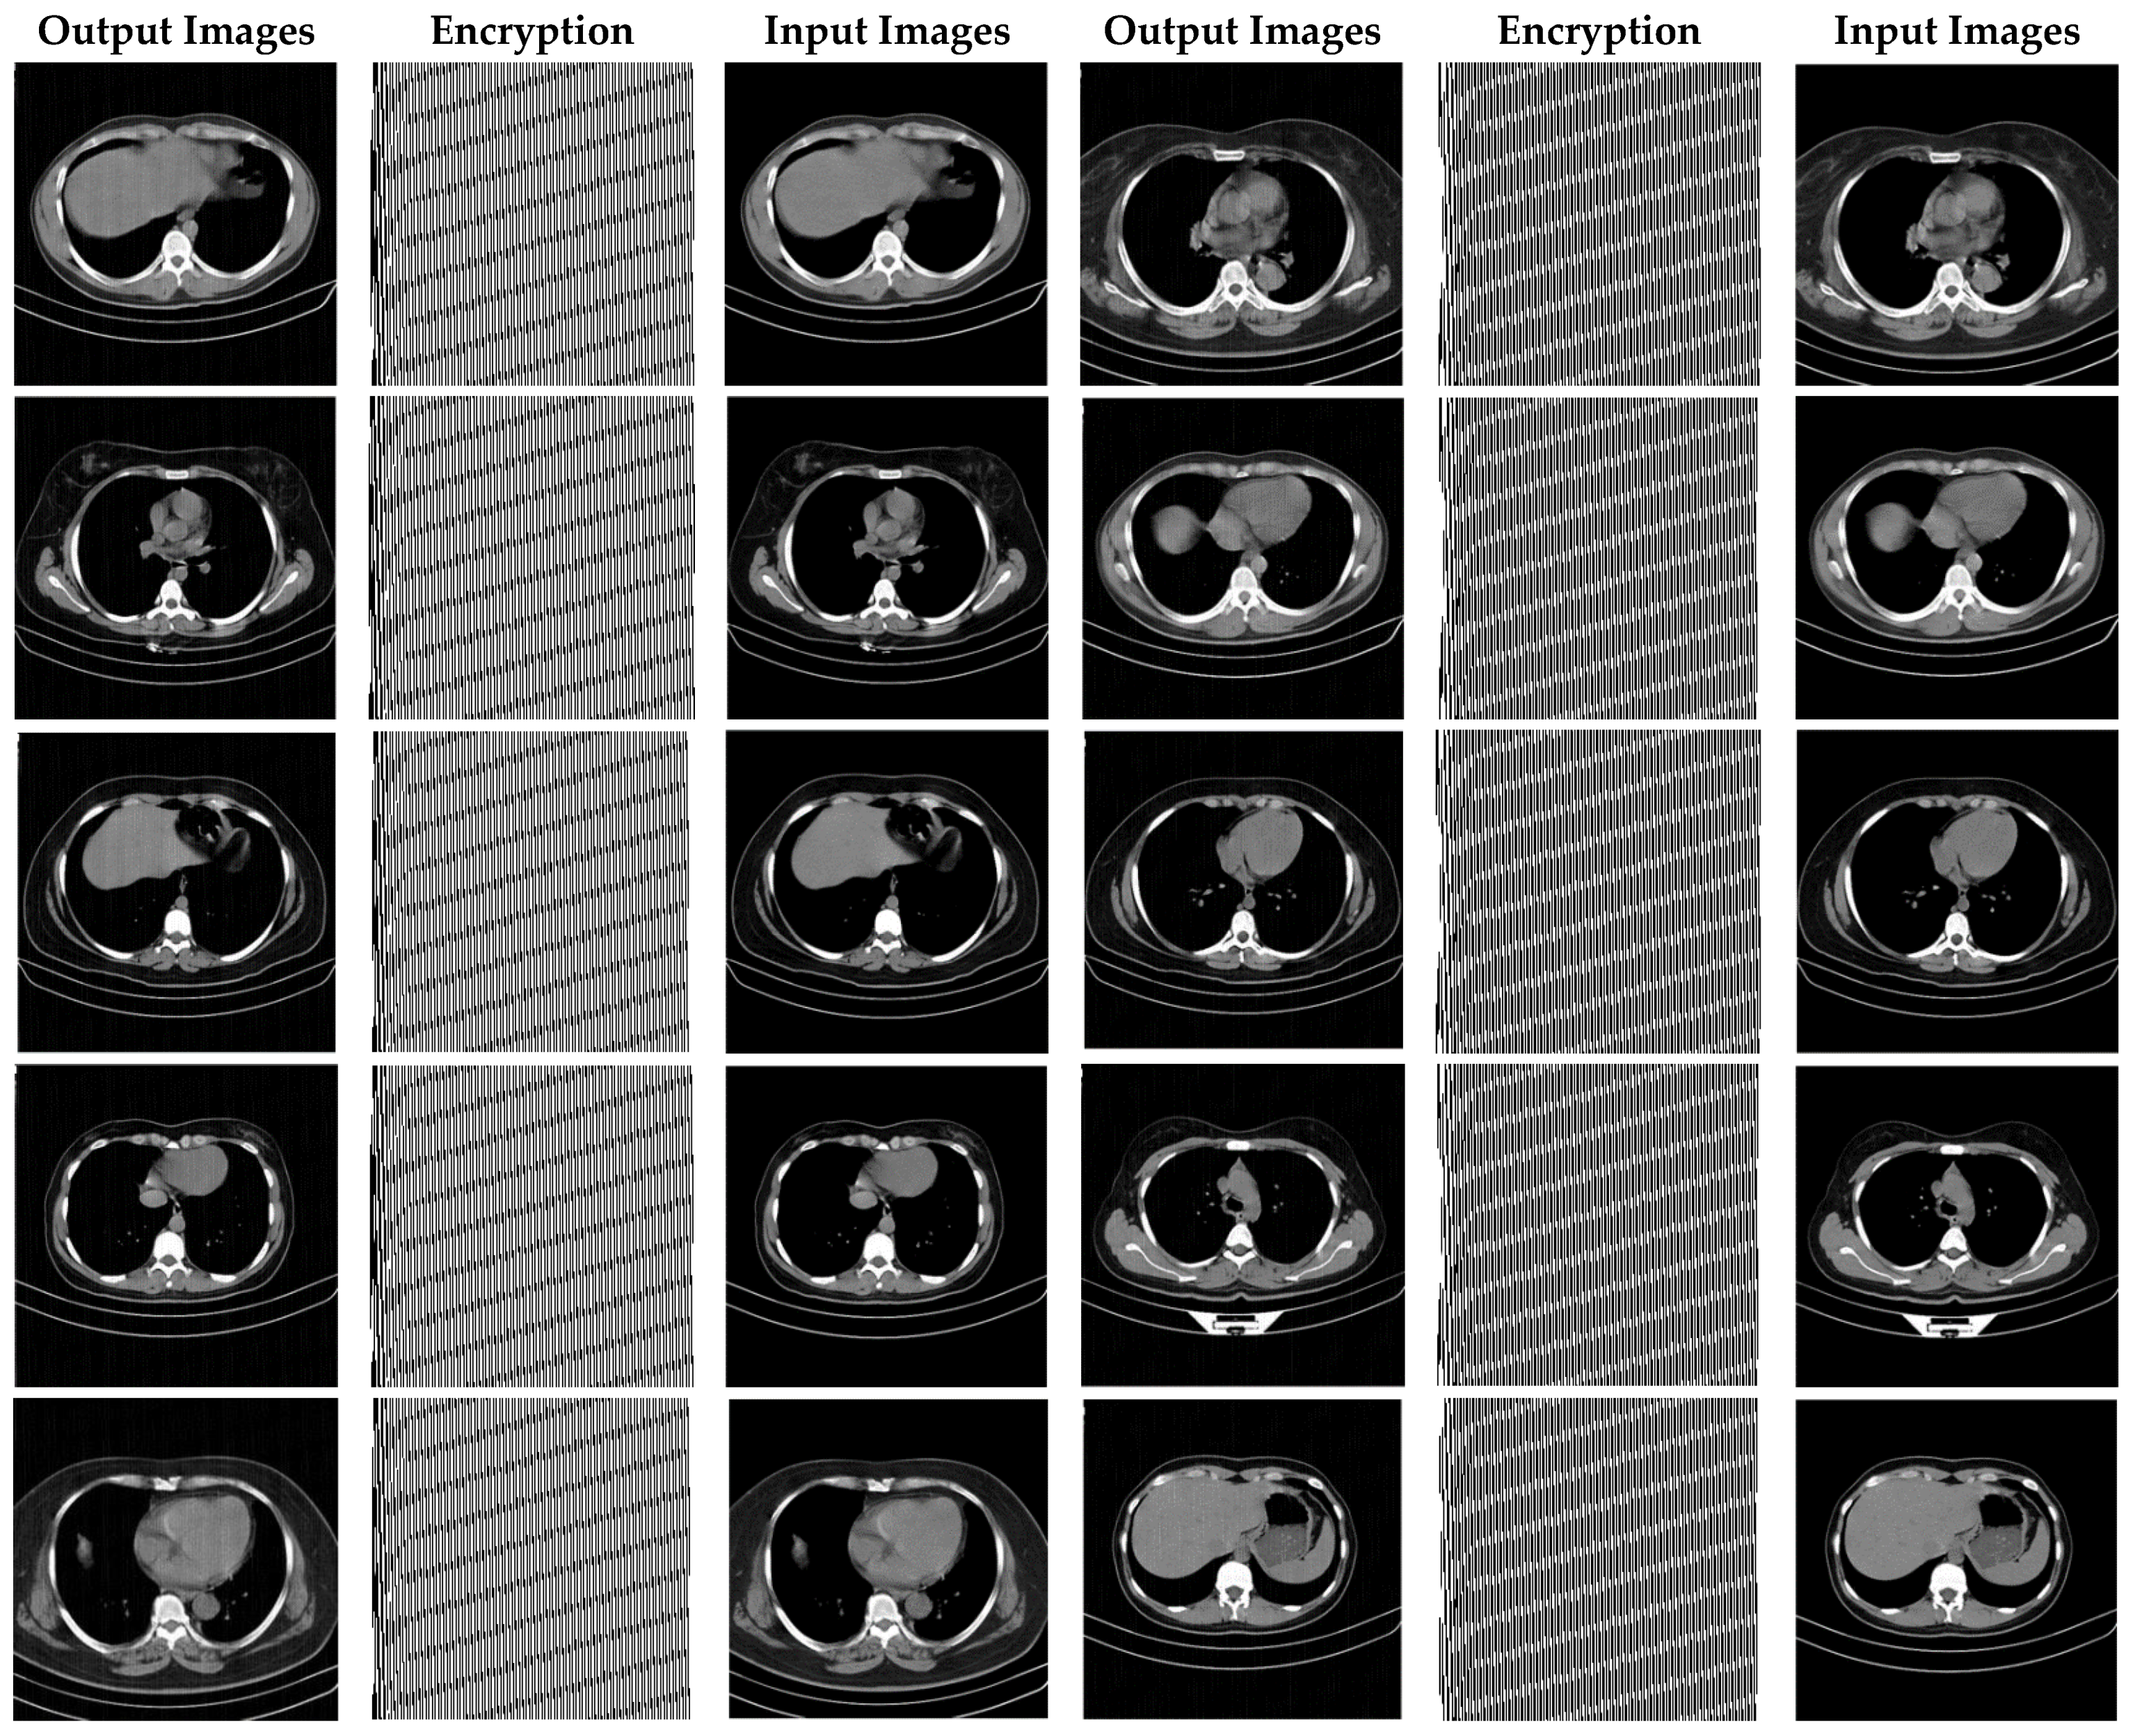

In this section, the results of the proposed synchronization method of chaotic systems for various images encryption are discussed. All images utilized in this research have a size of 300 × 300 in png format. Figure 14, Figure 15 and Figure 16 show encrypted images of standard benchmark, X-ray, and CT patients with COVID-19, respectively.

CT images encrypted using the proposed method.

Figure 16 demonstrates the various CT encrypted images. According to the figure, the CT images are first fed to the input of the proposed chaotic synchronization method. CT images encrypted are then generated. Finally, reconstructed CT images are represented. According to Figure 16, it can be seen that the cryptographic procedure based on synchronization of the proposed chaotic system achieves successful results.

As can be observed in Figure 16, the recommended method has also been very successful in CT images encryption of people with COVID-19. Additionally, with a conclusion, it is perceived that the cryptographic method based on synchronization of chaotic systems presented in this paper for various medical images and standard benchmarks achieves satisfactory results.